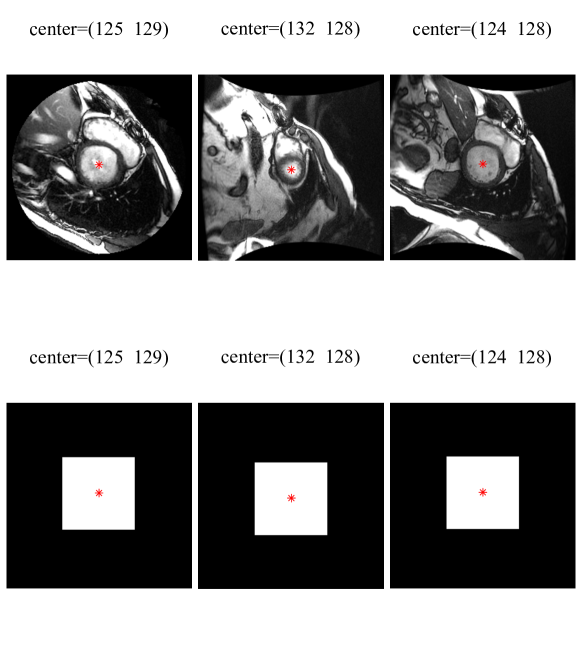

where is the labeled data corresponding to the th input image and is the number of training data. The labeled data at the output layer are binary masks, as shown in Fig. 4, generated based on manual training contours. As seen, a binary mask is an image with black background and a white foreground corresponding to the ROI. The foreground is centered at the center of the LV contour, which is known from the training manual contours. Note that the binary mask is down-sampled to and then unrolled as vector to be used for training.

where is the labeled data corresponding to the th image. The labeled data are binary masks created from manual segmentations drawn by experts. Fig. 5 depicts three examples of input images and corresponding labels used for training of the stacked-AE. Note that the binary mask is unrolled as vector to be used during optimization.